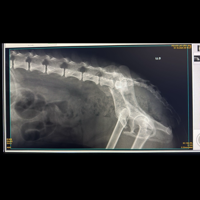

Resgatamos uma cadelinha das ruas em uma situação muito difícil… Ela precisa fazer uma cirurgia no quadril para voltar a andar sem dor e ter a vida cheia de amor que merece. 💔

Orçamento da clínica